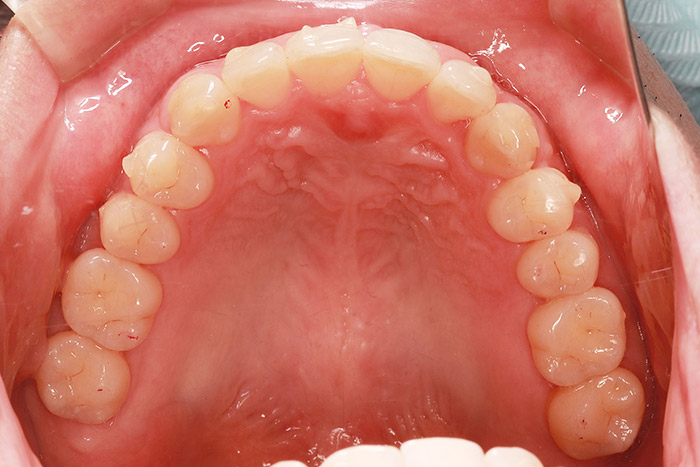

治療前

before

患者の症状 叢生、正中のずれ、上顎左右側切歯の口蓋側転位(交叉咬合)

治療方法 非抜歯で、マウスピース型カスタムメイド矯正歯科装置(インビザライン)による矯正

歯列弓を拡大することで非抜歯を可能にしました。

治療結果 側切歯の交叉咬合は解消、上下正中のずれも改善し咬み合わせが良くなりました。